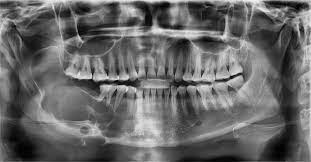

Jaw tumors and cysts

Jaw tumors and cysts are relatively rare growths or lesions that develop in the jawbone or the soft tissues in the mouth and face. Jaw tumors and cysts, sometimes called odontogenic tumors and cysts, can vary greatly in size and severity. These growths are usually noncancerous